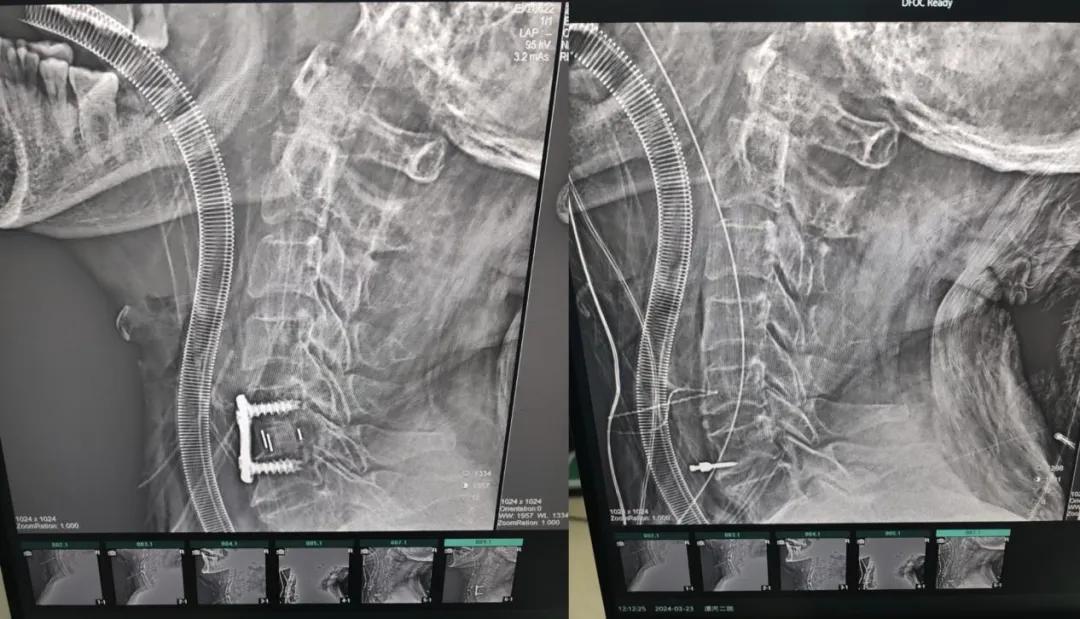

經(jīng)過縝密的術(shù)前準備和手術(shù)計劃,在鄭大一附院神經(jīng)外科張風(fēng)江教授的指導(dǎo)下,神經(jīng)外科團隊順利為患者實施“顯微鏡下頸椎前路C5/C6椎間盤切除椎間融合+內(nèi)固定術(shù)”,手術(shù)時間不到1小時。術(shù)后患者恢復(fù)情況良好。